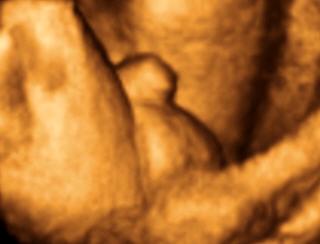

香港结构超声波照片

结构性超声波, 四维 香港, 四维结构性超声波 结构性超声波, 四维 结构性超声波, 四维 香港, 四维结构性超声波 结构性超声波, 四维 香港, 四维结构性超声波 结构性超声波, 四维 结构性超声波, 四维 结构性超声波, 四维 香港, 四维结构性超声波 结构性超声波, 四维 香港, 四维结构性超声波 结构性超声波, 四维 结构性超声波, 四维